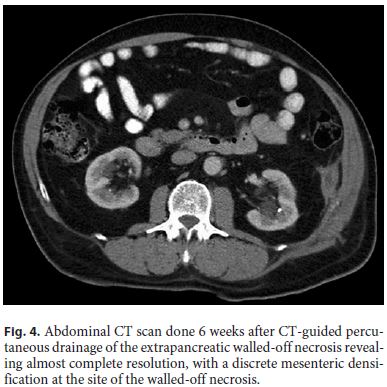

The patient was submitted to CT-guided percutaneous drainage of the collection with placement of an 8.5-Fr pig-tail catheter. Citrobacter freundii was isolated in the purulent fluid, susceptible to piperacillin/tazobactam, which was administered for 14 days. Three-times a day irrigation and washing of the WON with a 0.9% saline solution was performed. The patient reported symptomatic improvement, IP normalized, and the collection regressed (Fig. 3), so the drain was removed 15 days after its insertion and the patient was discharged.

A month later, radiologic imaging confirmed persistent resolution of the collection (Fig. 4).